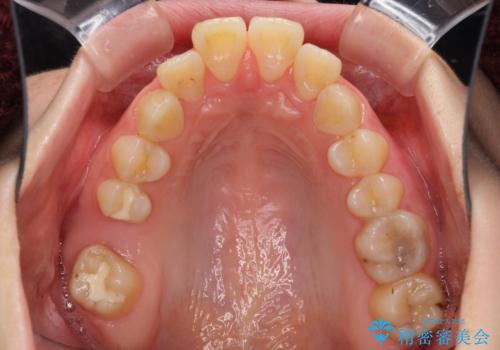

- 飛び出した上顎前歯を気にして来院された患者様です。

下顎は左右2番目の歯が2本欠損しており、上下前歯の前後的な位置は著しくずれている状態でした。

骨格的にも上顎骨が前突傾向にあり、極端な過蓋咬合になっていました。

強い咬合力に抵抗するように歯を動かす必要があるにもかかわらず、上顎第一大臼歯が1本欠損しているため、治療は困難を極めることが予想されました。

上顎前突を改善するために上顎左右第一小臼歯を抜歯し、補助装置を用いて上顎臼歯が前方に移動しないように工夫しながら、表側のワイヤー装置にて歯列を整えていくこととしました。